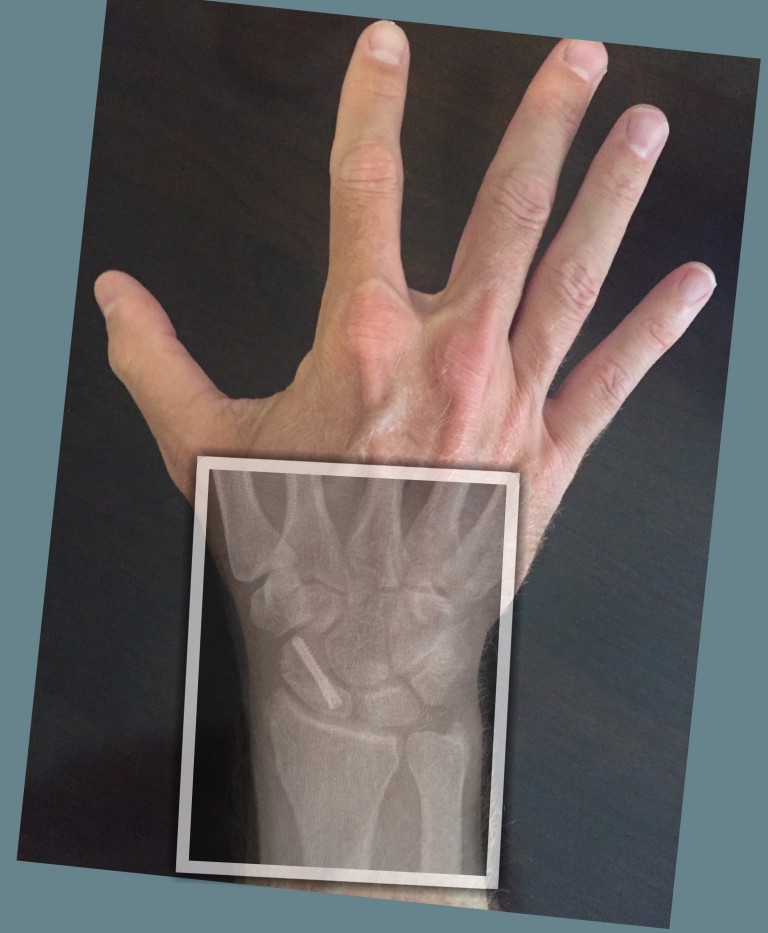

From www.researchgate.net

Radiograph of the left wrist shows stress fracture of the left scaphoid Can You Break Your Scaphoid If the scaphoid is broken, the few tiny blood vessels that supply the bone with nutrients can be damaged. This injury is initially treated simply in a wrist splint for 2 weeks to help reduce your pain. This type of break often causes pain and swelling on the thumb side of the wrist. They happen when you break your scaphoid. Can You Break Your Scaphoid.